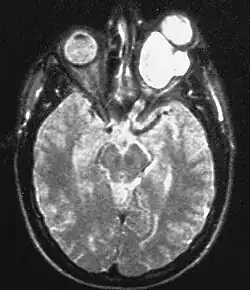

Magnetic resonance image of a large retrobulbar optic nerve tumor causing massive proptosis | |

Optic nerve gliomas are diagnosed using magnetic resonance imaging (MRI) and CT scans.[5] The tumor adopts a fusiform appearance, appearing wider in the middle and tapered at the ends.[5] Enlargement of the optic nerve along with a downward kink in the mid-orbit is usually observed.[5] While CT scans allow for optic nerve evaluation, MRI allows for intracranial evaluation to observe if the tumor has extended to other regions such as the optic chiasm and hypothalamus.[6]